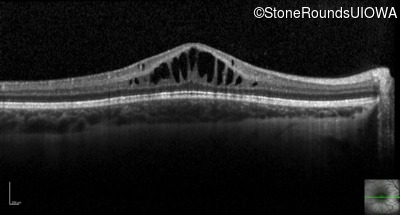

Optical Coherence Tomography - Left - 20/40

Exemplar / OCT Stack